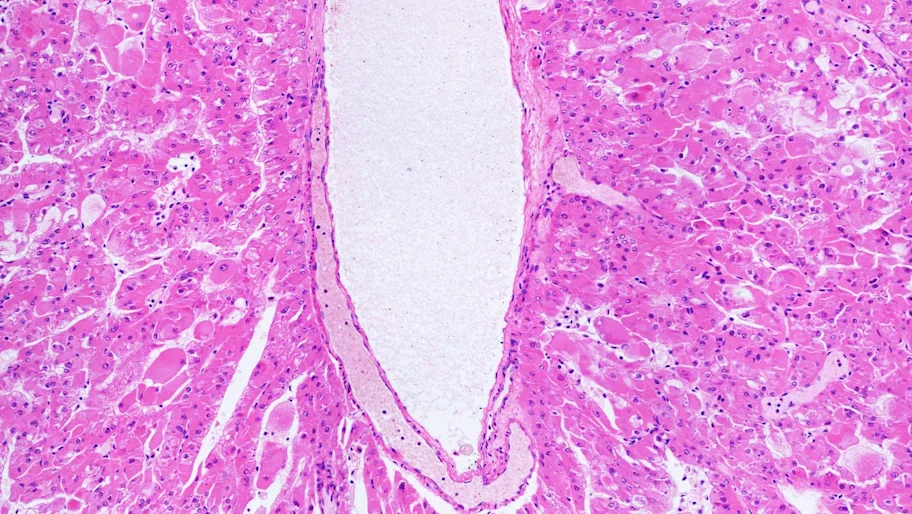

Cross-section of lymph vessel with a thin layer of Lymphatic Endothelial Cells (LECs) lining the inner cavity. Credit: Convit / Shutterstock.com

First, Fink and colleagues used microscopy to show that in tissue from healthy mice, primary cilia protrude from LECs towards the inside and outside of lymph vessels. Primary cilia are particularly common on LECs at the growth tip of vessels, where information from the microenvironment gets sensed. These observations suggest that LECs use their cilia to gauge their microenvironment, for example sensing the local strength of lymph flow or the presence of signaling molecules.